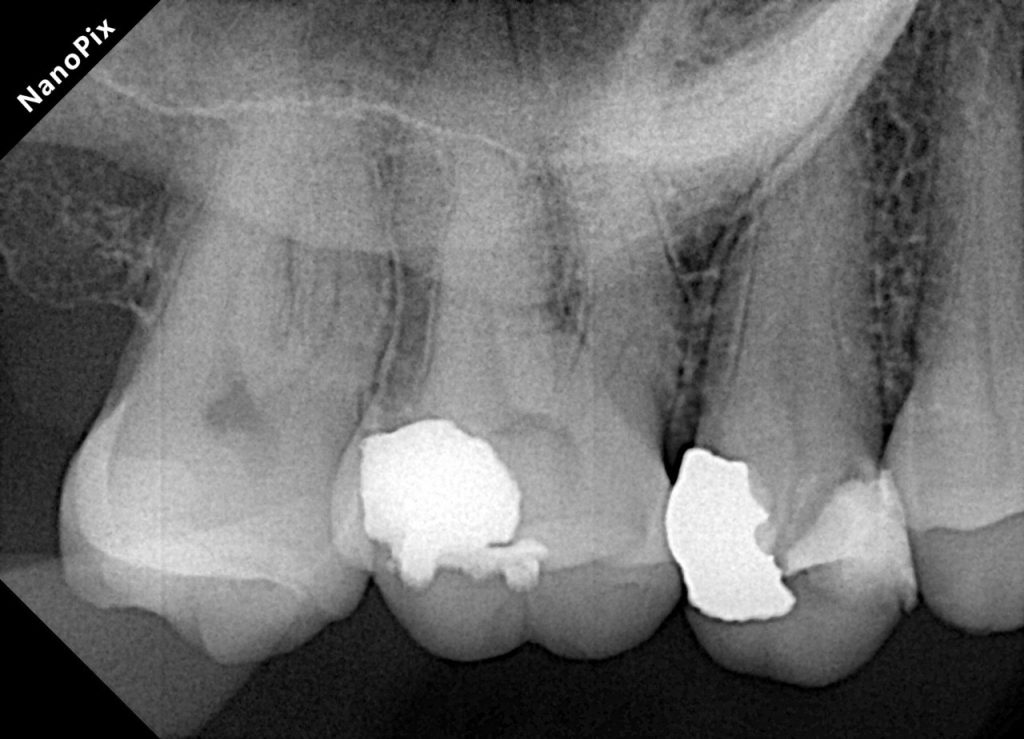

Diagnosis

Clinical and radiographic exam confirmed adjacent Class II carious lesions affecting both teeth, with secondary caries beneath existing composite and defective margins.

Defective composite and caries were removed in a controlled manner preserving sound enamel walls. Teflon floss ties and wooden wedges used for separation and gingival retraction (Fig 3–6).

- Preoperative occlusal view showing defective composite & caries

- Initial caries exposure and removal

- Proximal clearance and wedge placement